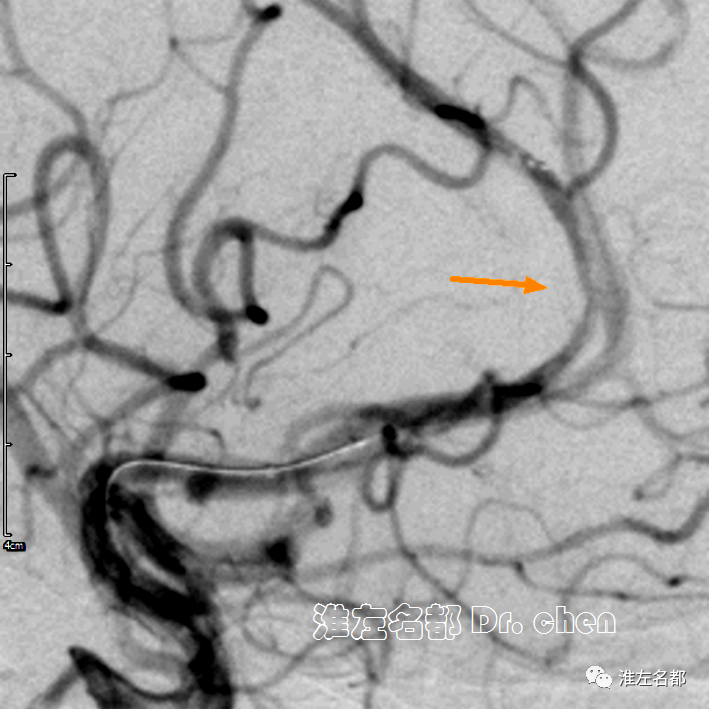

△经中间导管造影:左侧大脑前动脉A2段闭塞(橙箭)。

△经微导管释放取栓支架 S AB 4*20mm,造影:闭塞再通,局部管腔狭窄(橙箭)。

△30分钟后造影:左侧大脑前动脉前向血流良好,A3段局部中度狭窄(橙箭)